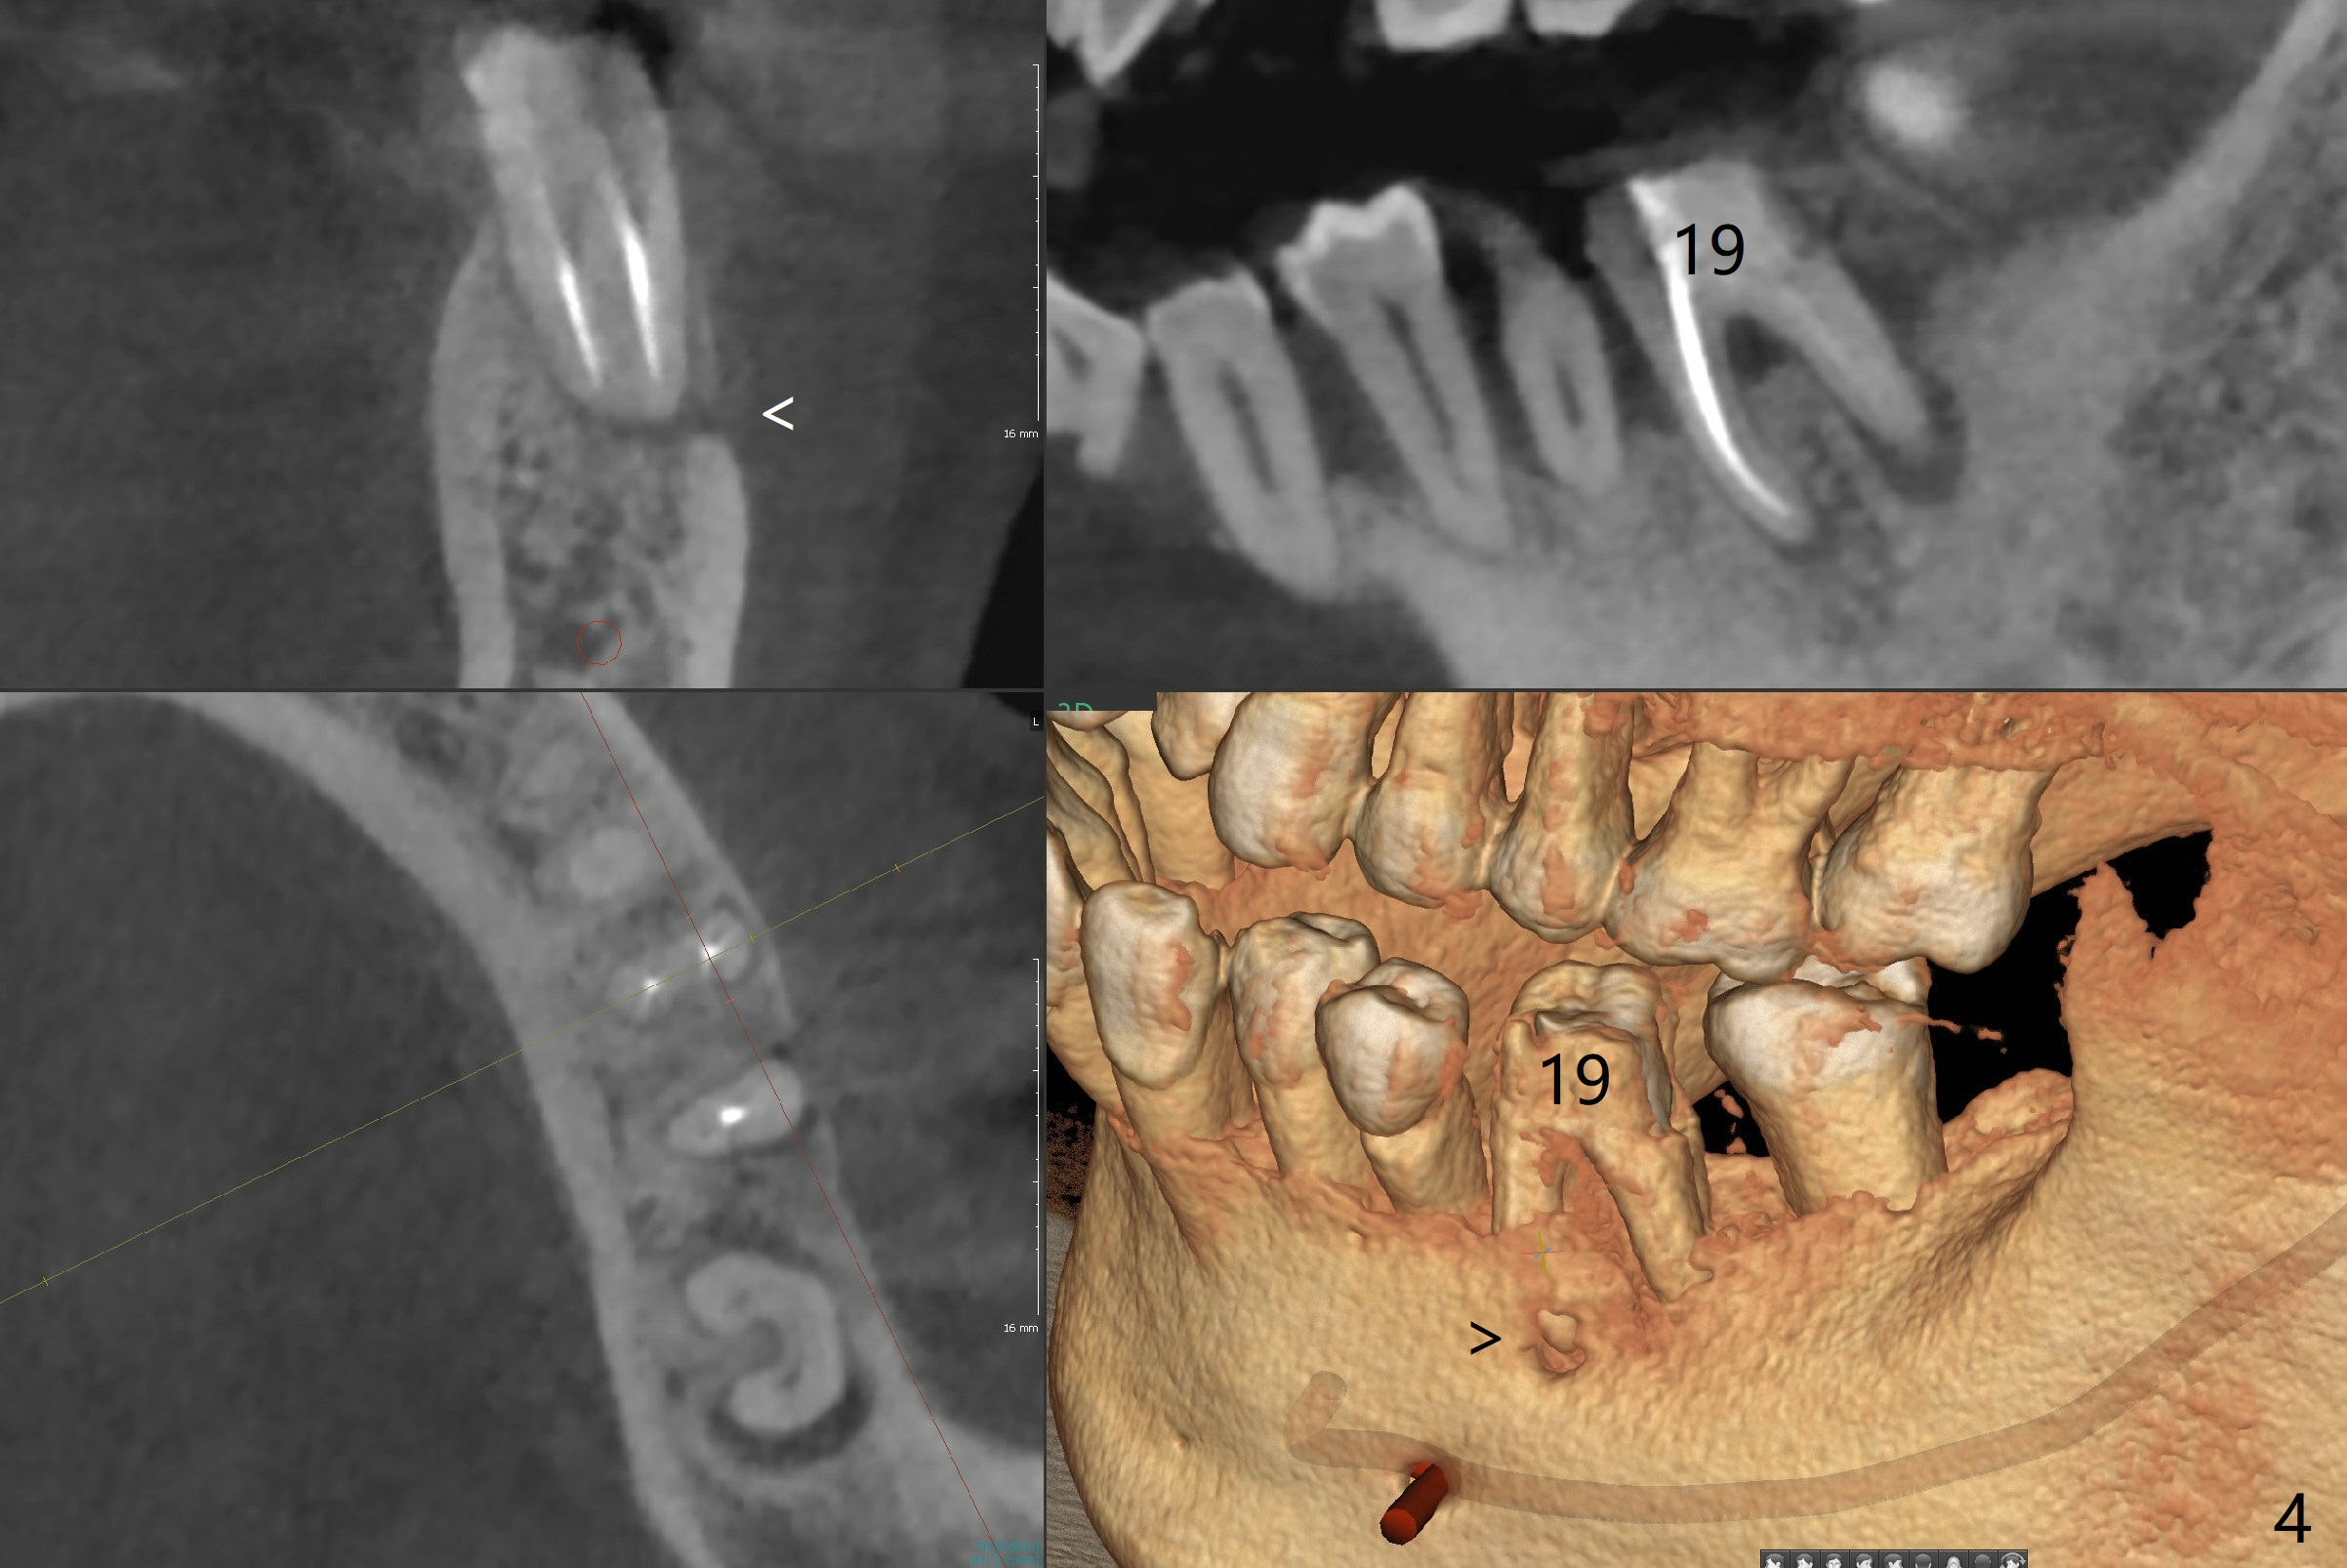

A 60-year-old man (smoker, 1/3 to 1/2 ppd) with large DO amalgam at #30 develops pain and mild swelling apparently apical to #29 (Fig.1-3). Both teeth (having fused PARL (periapical radiolucency) *) have mild percussion with the tooth #29 having higher mobility. CBCT shows apical defect (Fig.3 >). Three weeks earlier, the tooth #19 had much more severe infection with a similar apical defect (Fig.4 >). Combined with history of repeated infection associated with #30, the tooth is extracted with difficulty in obtain sound anesthesia. Socket preservation is performed instead of immediate implant (Fig.5 (*: Vanilla Graft)). CBCT makes it easy to diagnose 2 canals at #28 (Fig.6 as compared to Fig.2). Pain gradually decreases 3 days postop. In fact he has hypertension and smokes.